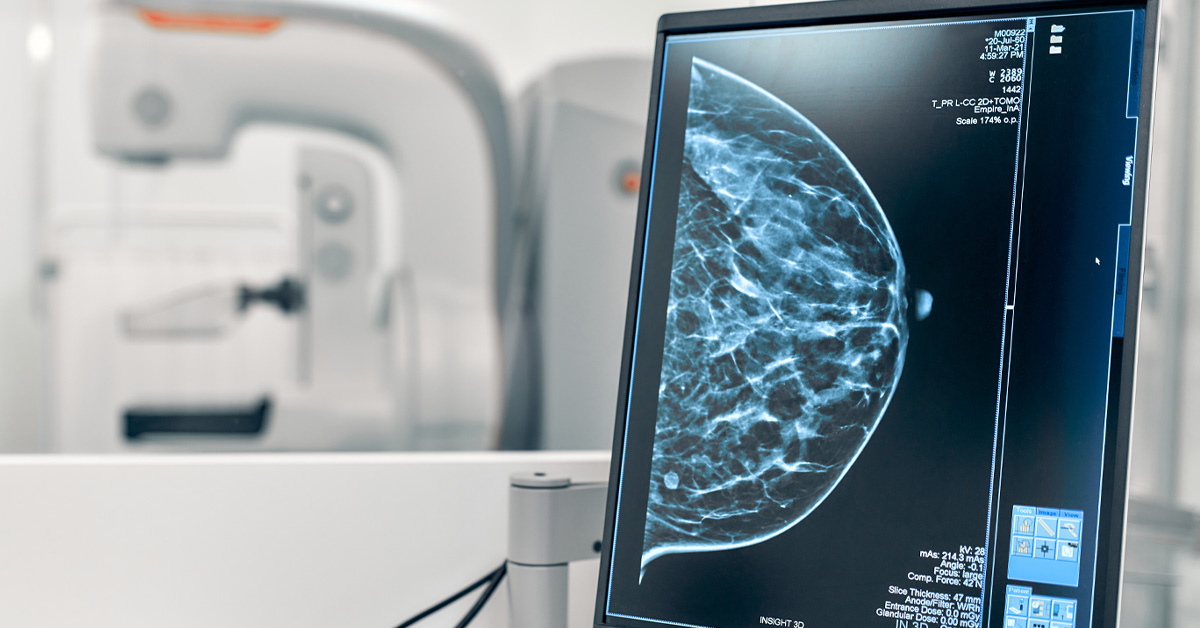

Skrining u ovom slučaju podrazumeva pregled na prvi pogled zdravih žena, kako bi se rano detektovale sumnjive promjene u tkivu dojke. Mamografija predstavlja rendgensko snimanje obe dojke, kako bi se otkrile abnormalnosti koje je nemoguće uočiti na drugi način. Procedura je bezbolna (ukoliko nema upalnih procesa) i kratko traje.